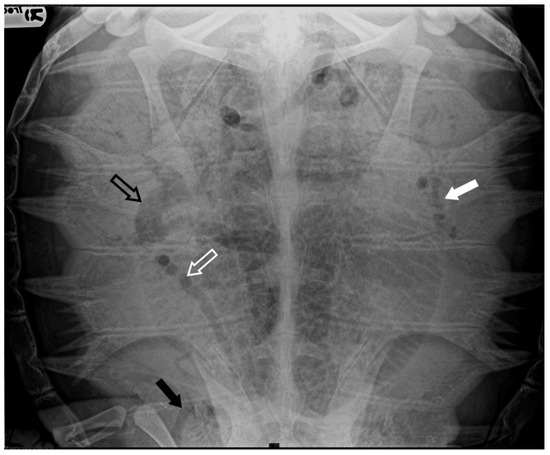

In four turtles (13, 8%), the ultrasound examination revealed a significantly slow blood flow, but no flow was detected using Color Doppler ultrasound. The renal vessels and subclavian vessels, which were closer to the acoustic windows, were easily identified. However, examination of the vessels and the coelomic cavity through the ventral cervical acoustic window was challenging due to significant gas-related disorders. Consequently, visualization of the aortic arch and the heart was precluded. Similarly, it was impossible to locate the mesenteric vessels and differentiate the hepatic parenchyma along with its associated circulation. The presence of larger emboli, some up to 5 mm in size, hindered the visualization of vessel walls, and the gas-induced artifacts, such as comet tails, were so pronounced that they masked the view of tissues and vascular regions (Figure 7) (Video S2). Those ultrasound images have been a consistent finding in the subjects previously categorized by radiographic exams as having moderate GE, implementing Parga’s method [17].

Figure 7.

Ultrasound scan from the right prefemoral window revealing several clusters of large emboli attached to the hepatic vessels (empty white arrows). The artifacts generated by their presence (white arrow) make it challenging to visualize deeper structures.

In six turtles (20, 7%), the ultrasound examination revealed a lack of blood flow, where no movement of emboli was detectable. Color Doppler ultrasound detected no flow in these cases. Vascular turbulence caused by the presence of macroemboli was frequent, yet visualization of vessel walls was unattainable. Neither organ parenchyma nor vascular sites could be identified in these cases. In our experience, those ultrasound findings were documented in turtles that have been radiographically classified as having severe GE.